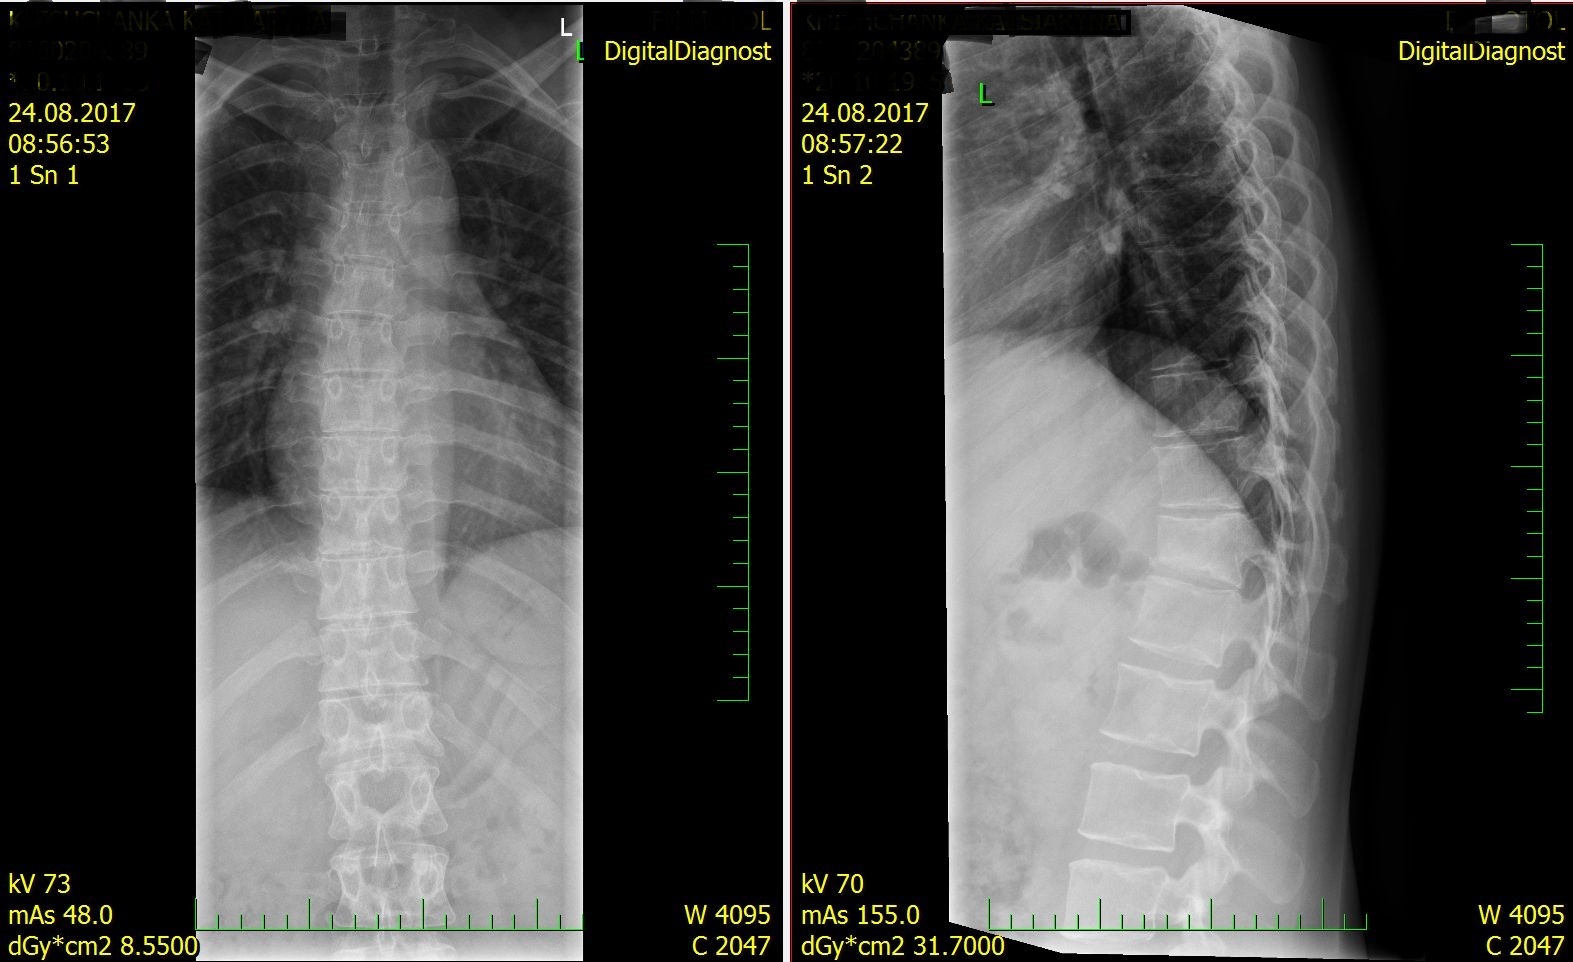

Компрессионный перелом T12, кленовидная деформация позвонка

24.08.2017 была на осмотре после трехнедельного лежания ( честно на костылях по квартире не передвигалась), сделали снимок, который отправляю Вам. Сказали, что нет ухудшение и нет улучшения и тут же предложили операцию. Я сказала, что не буду. У меня сколиоз с детства, мне сказали, что это плохо и навряд ли будет улучшение, будет расти горб и по итогу нужна операция. Так как много читала на наших форумах, спросила у врача про корсет. Сказал, что не надо, достаточно костылей. Я принимаю мумие два раза в день и лежу два раза по 30 мин на аппликаторе Ляпко. Первых дней 10 у меня болели бока, буквально недавно начали не сильные боли в области перелома и чуть выше, поясница если немного похожу.

клиновидная деформация позвонка ( компрессионный перелом 1 ст) есть. Чтобы оценивать динамику -нужно сравнивать снимки первые и последующие(Вы прислали только последние). Показания к оперативному лечению компрессионного перелома основывается и на снимках и на осмотре человека(который заочно не делается). В целом, если говорить не о коррекции сколиоза и массивной коррекционной операции в виде транспедикулярной фиксации, а о компрессионном переломе- то его ведение простое. Обычный рентген в динамике, чтобы оценить степень консолидации перелома и отсутствие дальнейшего снижения высоты тела позвонка с приемом медикаментов для коррекции боли-это консервативное лечение. При этом носится грудо-поясничный реклинатор в вертикальном положении. Либо плановое (с согласия пациента) малоинвазивное оперативное лечение - вертебропластика.